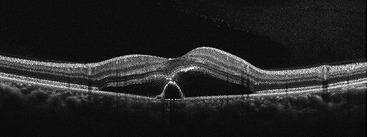

中心性漿液性脈絡網膜症

原因としては、ストレスや副腎ステロイド薬の副作用、妊娠が影響していると考えられています。

中心部がセピア色に見える・暗く感じる、軽度な視力低下、ピントが合わないなどの症状が現れることが多いです。両目に起こることもありますが、片目に起こることもあります。

治療としては、水分(漿液)を排出する作用のある内服薬の服用や、病変の位置によっては、レーザー治療を行います。当院では、必要に応じて連携する医療機関をご紹介しております。